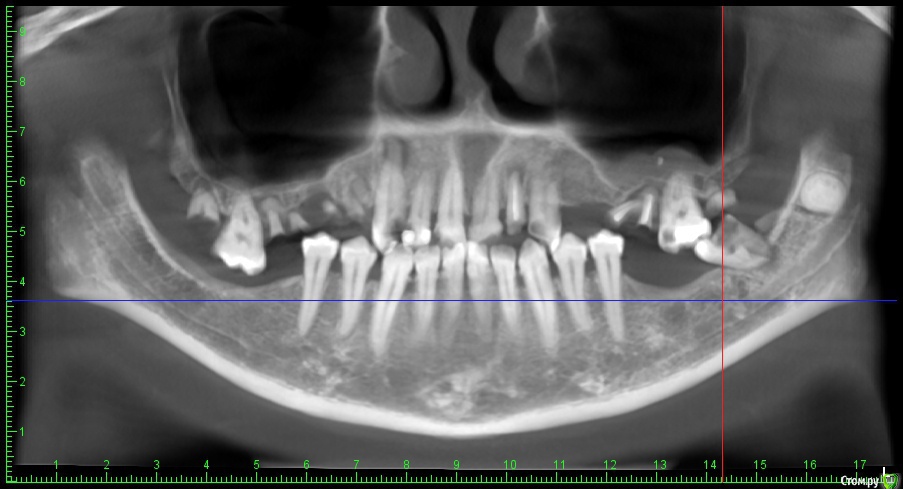

DenisV Опубликовано 18 декабря, 2019 Поделиться Опубликовано 18 декабря, 2019 Уважаемые коллеги, реферативный пациент, после химиотерапии окончил прохождение 2 месяца назад, хочет санировать полость рта (онколог разрешил), обнаружили образование на КТ в ретромолярной области слева. Какое Ваше мнение ? Направить к онкологу? Ссылка на комментарий

Lodkin666 Опубликовано 19 декабря, 2019 Поделиться Опубликовано 19 декабря, 2019 Мне кажется это похоже на сверхкомплектный зуб. Ссылка на комментарий

DenisV Опубликовано 19 декабря, 2019 Автор Поделиться Опубликовано 19 декабря, 2019 Мне кажется это похоже на сверхкомплектный зуб.неоднородной плотности, напрятали это зуб Ссылка на комментарий

Jurai Опубликовано 22 декабря, 2019 Поделиться Опубликовано 22 декабря, 2019 кажется, что зачаток сверхкомплектного или одонтома. Узнайте у пациента нет ли у него снимков прошлых лет - сравнить со свежим. Ссылка на комментарий

Irouil Опубликовано 22 декабря, 2019 Поделиться Опубликовано 22 декабря, 2019 Согласен, похоже на одонтому, чёткая капсула, плотность дентина 2 Ссылка на комментарий